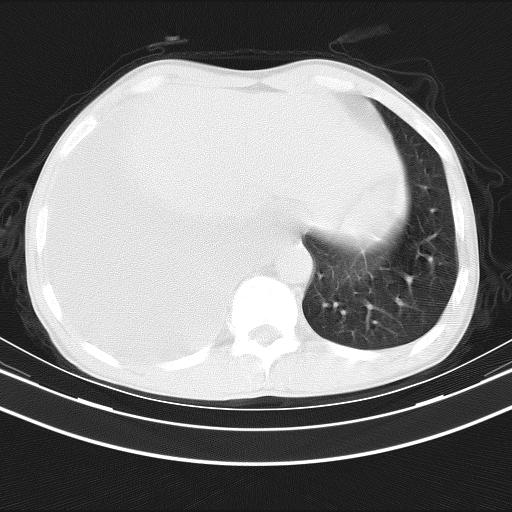

男性,44岁,结核病史多年。现胸闷气短,咳嗽,偶咳血。

右侧胸腔积液

右肺下叶不张

双肺多发结节影最分空洞形成考虑占位不除外结核

1、右侧大量胸腔积液伴右肺压缩性膨胀不全,建议抽液治疗后复查 2、两肺继发性tb伴空洞形成。

1)两肺继发性肺结核伴空洞形成,左肺多发性结核球。2)右侧大量胸腔积液伴右肺部分膨胀不全。3)纵隔淋巴结肿大。